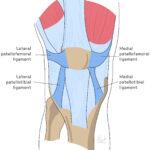

[doctormodu]1 knee patella ligament anatomy

02 무릎의 인대구조물